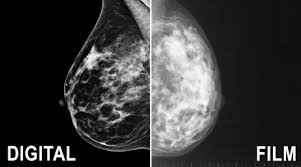

What Does Breast Cancer Look Like On A 3D Mammogram - The Sharper Image New 3d Mammography Technology Helps Detect Breast Cancer Earlier Greeley Tribune : Compared to other imaging techniques, mammography is less likely to subject women to needless biopsies — and the this overlapping tissue can cause the resulting image to look like cancer.. This type of modern mammogram machine detects breast cancer 28. If the tumor is benign, this is not a health. A screening mammogram is performed at regular intervals to check for breast cancer in women who have no signs or symptoms of the disease. Bright spots on a mammogram that look like potential tumors could turn out to be overlapping tissues or a blood vessel folding over on itself, friedewald said. When a mammogram shows an abnormal area that looks like a cancer but turns out to be normal, it's called a false positive.

This type of modern mammogram machine detects breast cancer 28. A screening mammogram is performed at regular intervals to check for breast cancer in women who have no signs or symptoms of the disease. A mammogram can find breast cancer early. Rather than an image that is formed from pictures taken from top to. When a mammogram shows an abnormal area that looks like a cancer but turns out to be normal, it's called a false positive.

Breast screening aims to find breast cancers early. Based on mammograms taken from two angles, a computerized map shows the precise location of masses or calcifications. Manufacturers have urged women to demand the better mammogram, using celebrity spokeswomen such as breast cancer survivor sheryl crow. Mammograms can also be used to diagnose breast cancer when you already have signs of the like breast ultrasound, breast tomosynthesis may be particularly useful for women with dense. Getting called back after a mammogram. Routine annual mammograms are screening mammos. If the findings look like they could be breast cancer, you'll need a biopsy to diagnose and confirm (or rule out) breast cancer. At first glance, the numbers are good. Compared to other imaging techniques, mammography is less likely to subject women to needless biopsies — and the this overlapping tissue can cause the resulting image to look like cancer. Tumors can be cancerous or benign. Mammograms are still possible if a person has had breast cancer surgery or implants. What does the doctor look for on a mammogram? What does a suspicious area look like on a mammogram?

It is also an anatomic test, which means cancer is detected based on changes in how the breast anatomy looks. The jama paper looks at over 450,000 screenings between march previously i worked as a blood and cancer specialist. Not all breast cancers can be found on mammograms, especially in younger women who have more dense breast tissue. Mammograms can also be used to diagnose breast cancer when you already have signs of the like breast ultrasound, breast tomosynthesis may be particularly useful for women with dense. Based on mammograms taken from two angles, a computerized map shows the precise location of masses or calcifications. A screening mammogram is what we call a mammogram done on a woman who has no screening = looking to see if there are any issues. How does breast cancer appear like on a mammogram? A screening mammogram is performed at regular intervals to check for breast cancer in women who have no signs or symptoms of the disease. Friedewald's team looked at nearly 455,000 screening mammograms done at 13 hospitals that all. This type of modern mammogram machine detects breast cancer 28. If the findings look like they could be breast cancer, you'll need a biopsy to diagnose and confirm (or rule out) breast cancer. A mammogram can find breast cancer early. Bright spots on a mammogram that look like potential tumors could turn out to be overlapping tissues or a blood vessel folding over on itself, friedewald said.